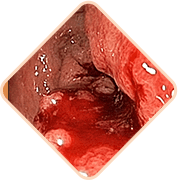

Az aranyér 3 halálosan veszélyes következménye, ha nem kezeli a problémát

Bármelyik a lent felsoroltak közül

a beteg hirtelen halálát okozhatja!

A széklet hatalmas mennyiségű mikrobát, baktériumot és gombát tartalmaz. Ha a fertőzés bejut a kismedencei szövetekbe és a szomszédos szervekbe, veszélyes gyulladás és vérmérgezés is lehetséges

Az aranyeres csomók megtelt erei nagyon gyengék. Gyakran szétszakadnak. A vérveszteség mértéke ebben az esetben olyan lehet, hogyvérátömlesztésre is sor kerülhet

Az erekbe vérrögök jöhetnek létre. Ezek a vérrögök leszakadhatnak a vénák falairól és elzárhatják a belső szervekhez vezető ereket, megzavarva így a vérkeringést, és elzárhatják a pulmonalis artériákat.Ebben az esetbne nagy a halál valószínűsége